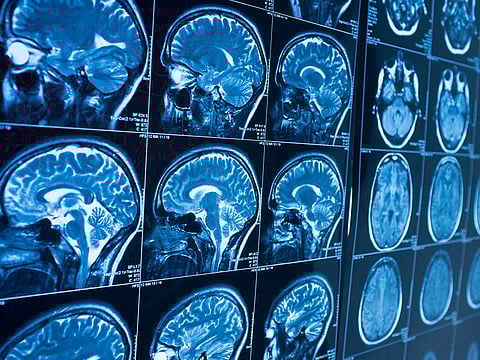

With each MRI scan, the tumour’s complete disappearance astonished medical experts.

“Over a series of MRI scans, I watched as the tumour completely disappeared," Dr Grill told AFP.